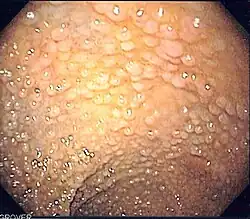

O câncer colorretal é um exemplo em que o tumor é formado pelo defeito na comunicação célula-célula. Sabe-se que a adesão célula-célula desempenha um importante papel na manutenção da homeostase do tecido epitelial; uma desorganização dessa adesão influencia no desenvolvimento da carcinogênese, nesse caso no epitélio do reto. Essa adesão, como dito anteriormente, é favorecida pela caderina; no caso do epitélio retal, é a E-caderina quem exerce esse papel. Durante o processo de formação do câncer é observada uma expressão diminuída da E-caderina ou sua translocação da membrana plasmática para o citoplasma, causando uma desorganização da adesão célula-célula. Essa desorganização da adesão célula-célula pode ser mediada por diversos fatores, como por exemplo a endocitose de E-caderina ou a clivagem do domínio extracelular da E-caderina, resultando na E-caderina solúvel e na liberação do domínio intracelular para o citoplasma. Essa redução na expressão de E-caderina vai indicar um aumento na invasividade tumoral, sendo um tumor mais maligno, e também está correlacionada a um aumento na probabilidade de metástases e na mortalidade do paciente. Também foi descoberta uma relação entre as vias de sinalização celular envolvendo proteínas quinases (PKA) e GTPases, que são responsáveis por regular a organização do citoesqueleto de actina e das junções intercelulares, onde a E-caderina cumpre seu papel.[79]